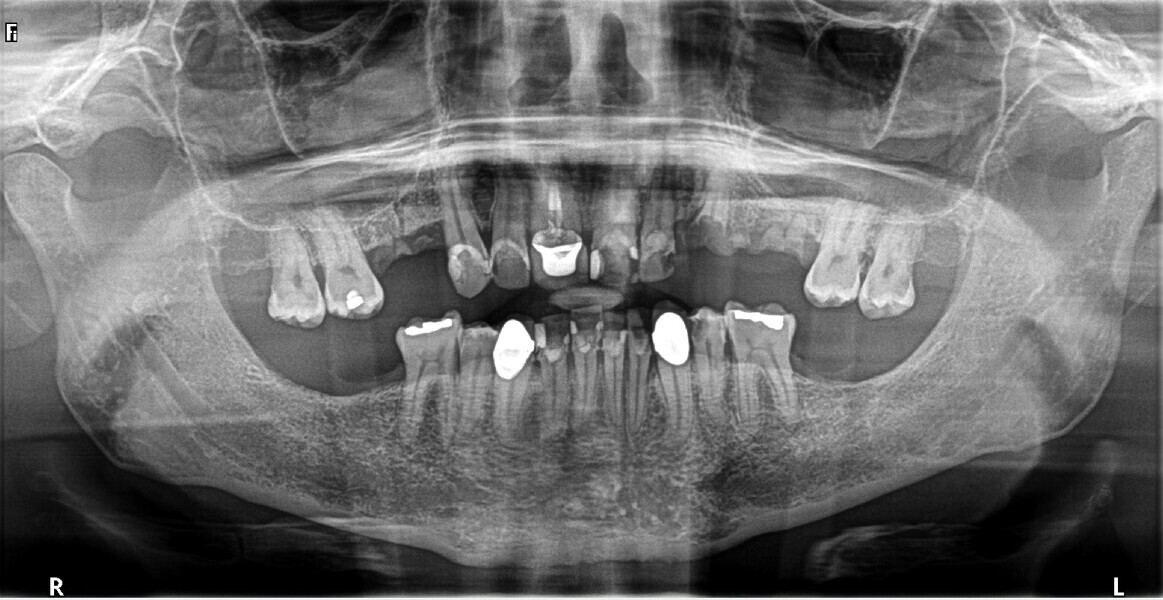

Fig. 1: Pre-op retracted frontal view.